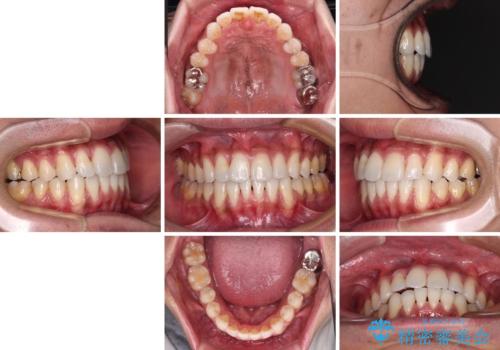

上顎の狭い歯列をインビザラインで拡大

- 上下前歯の叢生を気にして来院された患者様です。

奥歯はクロスバイトとなっているので上顎は側方拡大を行いつつ、上下全体の叢生をインビザラインにより改善することとしました。

治療途中でクリーニングやホワイトニングを行い、歯列が整うと同時に明るい口元となりました。